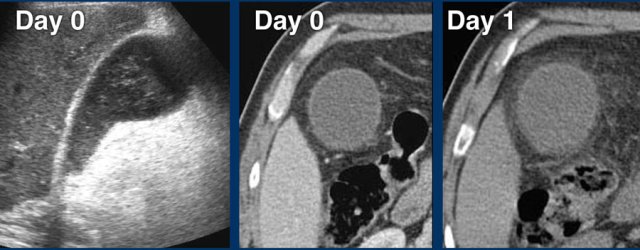

At day 0 there is acute hydrops due to an impacted stone.

One day later, the patient is symptom free.

The stone is still in place, but apparently allows passage of bile to the cystic duct, since hydrops has disappeared.

Reperfusion edema and sludge are the silent witnesses of the previous attack .

CRP remained normal.